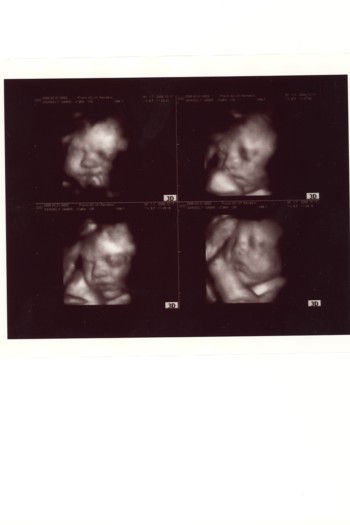

Rakok fel Flóráról képet.Egyre inkább hasonlít az apukájára! Kép

Tegnap 2880grammosra mérték, hát nemtudom mekkora lesz! :shock: